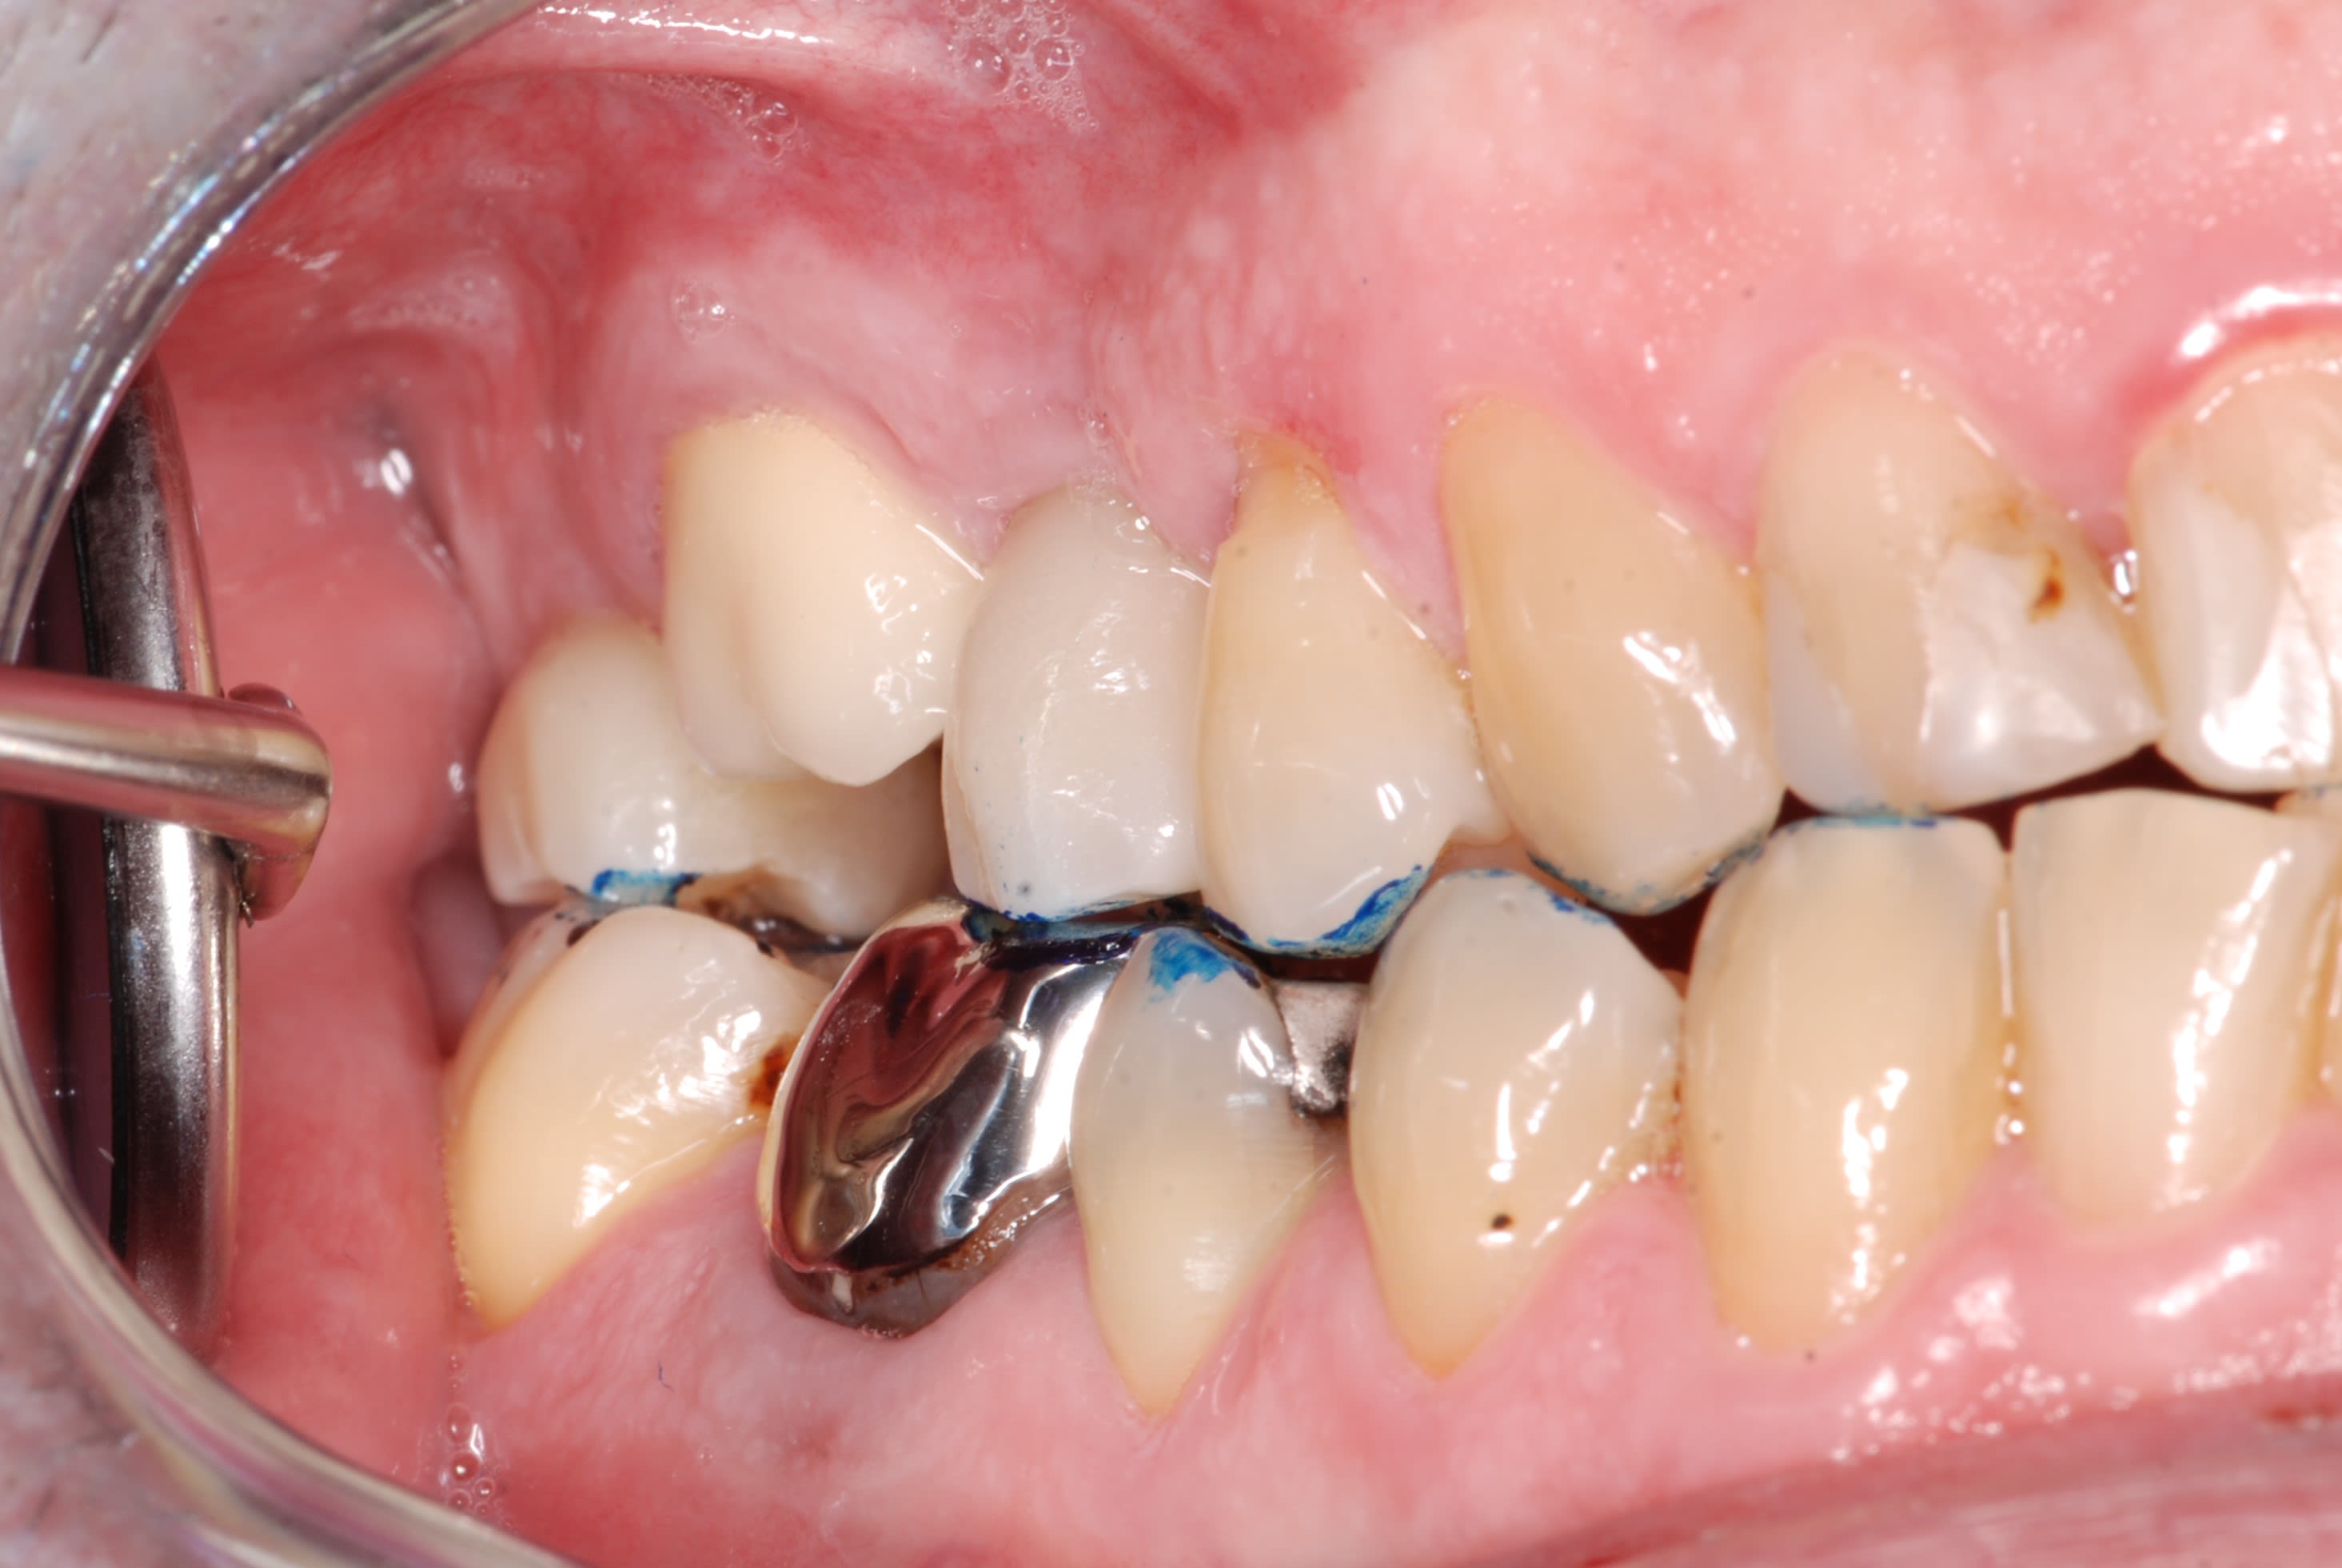

Comme promis, voici les photos du cas.

Comme je disais on dirait que la dent est remontée avec tout son parodonte...

Rien de particulier de noté au cbct fait par mon correspondant implanto. je vais lui demander les coupes

Oui point de contacts encore présents et bien serrés, le fil claque bien avec douleurs au passage du fil.

pourtant , sa couronne "fer" est toute mate en distal , pourquoi ? on dirait qu il y a ou qu il y a eu frottement mais pas avec un truc dur . .

et sa ceram , elle est cassée en distal ?